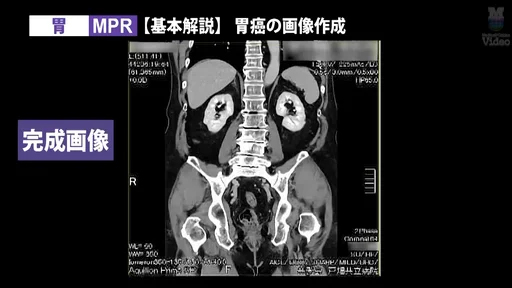

3D画像作成の人気シリーズに、「胸郭出口症候群(TOS)」と「胃」の新作を追加。CT撮影から3D画像作成までの流れを、実際の画面キャプチャを交えて徹底解説する。

監修:山本晃義先生(戸畑共立病院)/実演・解説:田原琢朗先生

3D画像作成技術をさらに磨きたい放射線技師に向けた、実践的な内容である。